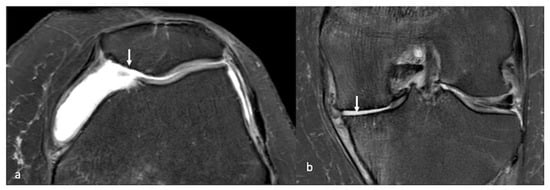

- Gorbachova, T.; Melenevsky, Y.; Cohen, M.; Cerniglia, B.W. Osteochondral Lesions of the Knee: Differentiating the Most Common Entities at MRI. Radiographics 2018, 38, 1478–1495. [Google Scholar] [CrossRef]

- Smet, A.A.D.; Ilahi, O.A.; Graf, B.K. Reassessment of the MR criteria for stability of osteochondritis dissecans in the knee and ankle. Skeletal. Radiol. 1996, 25, 159–163. [Google Scholar] [CrossRef] [PubMed]